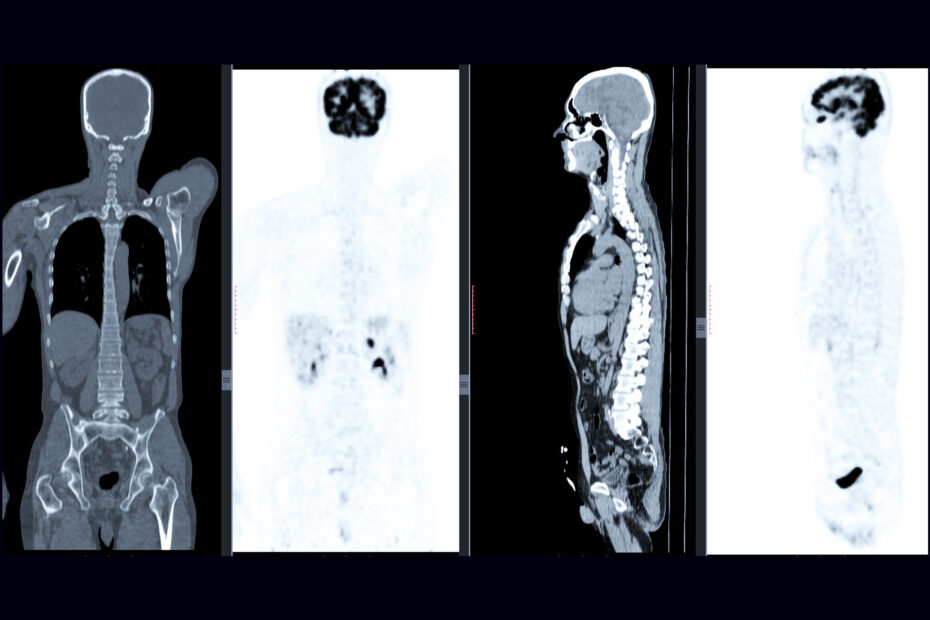

Dopo l’iniezione endovenosa del radiofarmaco, il paziente viene posizionato all’interno sul lettino di un tomografo PET (molto simile al macchinario usato per le TAC), dove vengono acquisite diverse immagini che riflettono la distribuzione e l’intensità dell’assorbimento del tracciante nei diversi distretti corporei.

La PET è associata a una tomografia computerizzata (TC), che permette la fusione delle immagini funzionali (derivate dalla PET) e anatomiche (derivate dalla TC), migliorando la localizzazione delle aree di ipercaptazione del radiofarmaco.